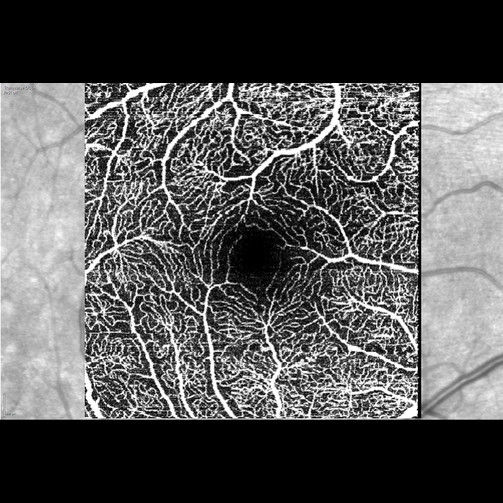

8.Módulo de Angiografia OCT

Imagem vascular não invasiva

O Módulo de Angiografia OCT SPECTRALIS® oferece imagens de OCTA de alta resolução, com uma resolução lateral de 5,7 μm/pix. Combinado com a precisão do TruTrack Active Eye Tracking, o módulo OCTA permite visualizar redes capilares finas com grande detalhe.

A resolução axial de 3,9 μm/pixel permite a segmentação de todos os quatro plexos vasculares da retina validados histologicamente. Lâminas personalizadas dentro dos plexos vasculares superficial e profundo oferecem uma avaliação clínica mais abrangente.

A ferramenta de remoção de artefatos de projeção (PAR) utiliza informações do plexo vascular superficial para remover artefatos das imagens OCTA. Isso possibilita uma visualização mais precisa da estrutura vascular e das patologias.

• Campo de visão flexível

• Remoção de Artefatos de Projeção (PAR)

• Angiografia Hibrida

• Imagem Multimodal com OCTA